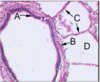

What type of ciliated epithelium is this?

What is the arrow pointing to?

What are the arrow heads pointing to?

Simple columnar

Smooth muscle

BALT